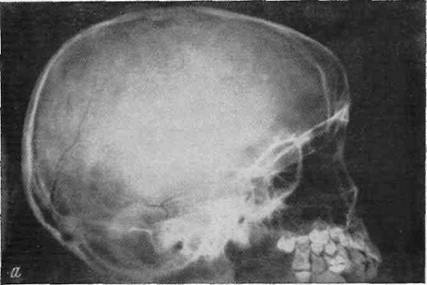

Внаслідок ДТП пасажир автомобіля, жителька м. Калуш, 1999 р.н., отримала перелом кісток черепа.